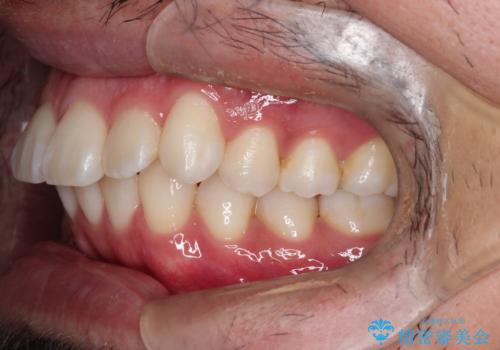

【インビザライン】前歯の凸凹を解消。

- 前歯の凸凹を主訴に来院されました。

もともと、顎が左にシフトしていたので正中が合わないことを説明した後、矯正を開始しています。

短期間で前歯のがたがたがきれいになり、満足していただけました。

顎が偏移している場合は、正中やかみ合わせは正常と比べずれた位置での仕上がりとなります。